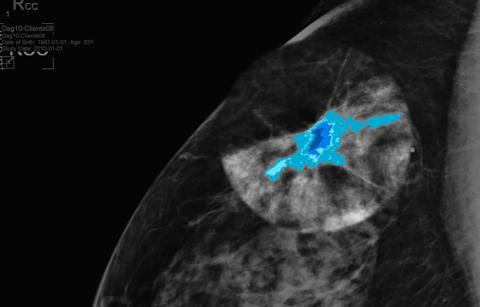

How does it work? DL Precise augments an area you choose with a vividly colored density map. With one additional click, you get immediate segmentation and measurements of the object.

DL Precise goes beyond the range of human vision. It makes consistent measurement of a region over time easier and enables coordinated collaboration. It works on demand: you choose whether you activate it and which area you wish to inspect.

The colored density maps that DL Precise shows use Barco’s unique SteadyColor technology. Contrast, colors and detail are shown in a consistent way, which make the tool ideal to use for consistent follow-up measurements of a mass over a longer period of time.